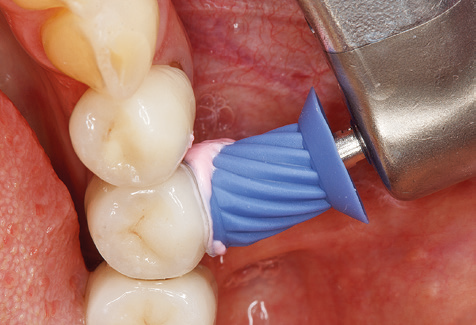

Of course, the use of instruments for mechanical removal of the biofilm is a central component of SPT and thus of primary significance. Consequently, the SPT workflow comprises both supragingival and subgingival cleaning. In our concept, a combination of hand instruments and machine cleaning has proven advantageous. A number of options are available for the mechanical procedures: sonic devices, ultrasonic devices and powder jet devices.

Good illumination of the working field facilitates the process considerably. The system used by the authors achieves this thanks to a 5x LED ring integrated in the handpiece. Naturally, a range of working tips for different indications is also offered. A straight, universally employable tip is the basic instrument required for machine cleaning of natural teeth (Fig. 5a and b). Curved tips, which allow access to exposed furcations, are also available for hard-to-reach areas in the posterior region (Fig. 6).

Of course, working tips for the cleaning of implant surfaces are also indispensable for SPT in patients fitted with implants. The implant cleaning attachment on the system used here is characterised by its tapered, hexagonal design. This design allows light, atraumatic penetration of the peri-implant pocket and displays a good cleaning performance (Fig. 7).

Following machine cleaning of the tooth and implant surfaces, the surfaces of the natural teeth are cleaned manually using standard hand instruments. When performing manual cleaning, particular attention must be given to maintaining the correct angle of application, appropriate sharpness, good support and working with the curette from apical to coronal. Either titanium or carbon curettes should be used for post-cleaning of the implant structures (Fig. 8). In addition to the use of ultrasonic devices, power jet devices can also be used in conservative dentistry. However, it must be taken into consideration that these procedures are not suitable for removing hard deposits and thus they cannot replace the use of hand instruments and ultrasonic instruments completely. In all cases, cleaning is followed by mechanical polishing of the accessible tooth and implant surfaces with polishing cups and polishing compounds (Fig. 9).

Fig. 4: Flexible probes with millimetre markings are recommended for the probing of dental implants (e.g. Colorvue Kit PCV11KIT6, Hu­Friedy). – Fig. 5a and b: A straight working tip (1P, W&H Dentalwerk Bürmoos GmbH) is a suitable instrument for use on all natural teeth. – Fig. 6: Curved working tips (3Pr/3Pl, W&H Dentalwerk Bürmoos GmbH) lend themselves to the processing of difficult-to-reach areas of the tooth and root surfaces (e.g. furcations). – Fig. 7: The tapered, hexagonal implant cleaning tip (1I, W&H Dentalwerk Bürmoos GmbH) permits atraumatic and efficient cleaning of the crown and abutment surfaces. – Fig. 8: Titanium and carbon curettes are suitable instruments for the manual cleaning of the implant surfaces.